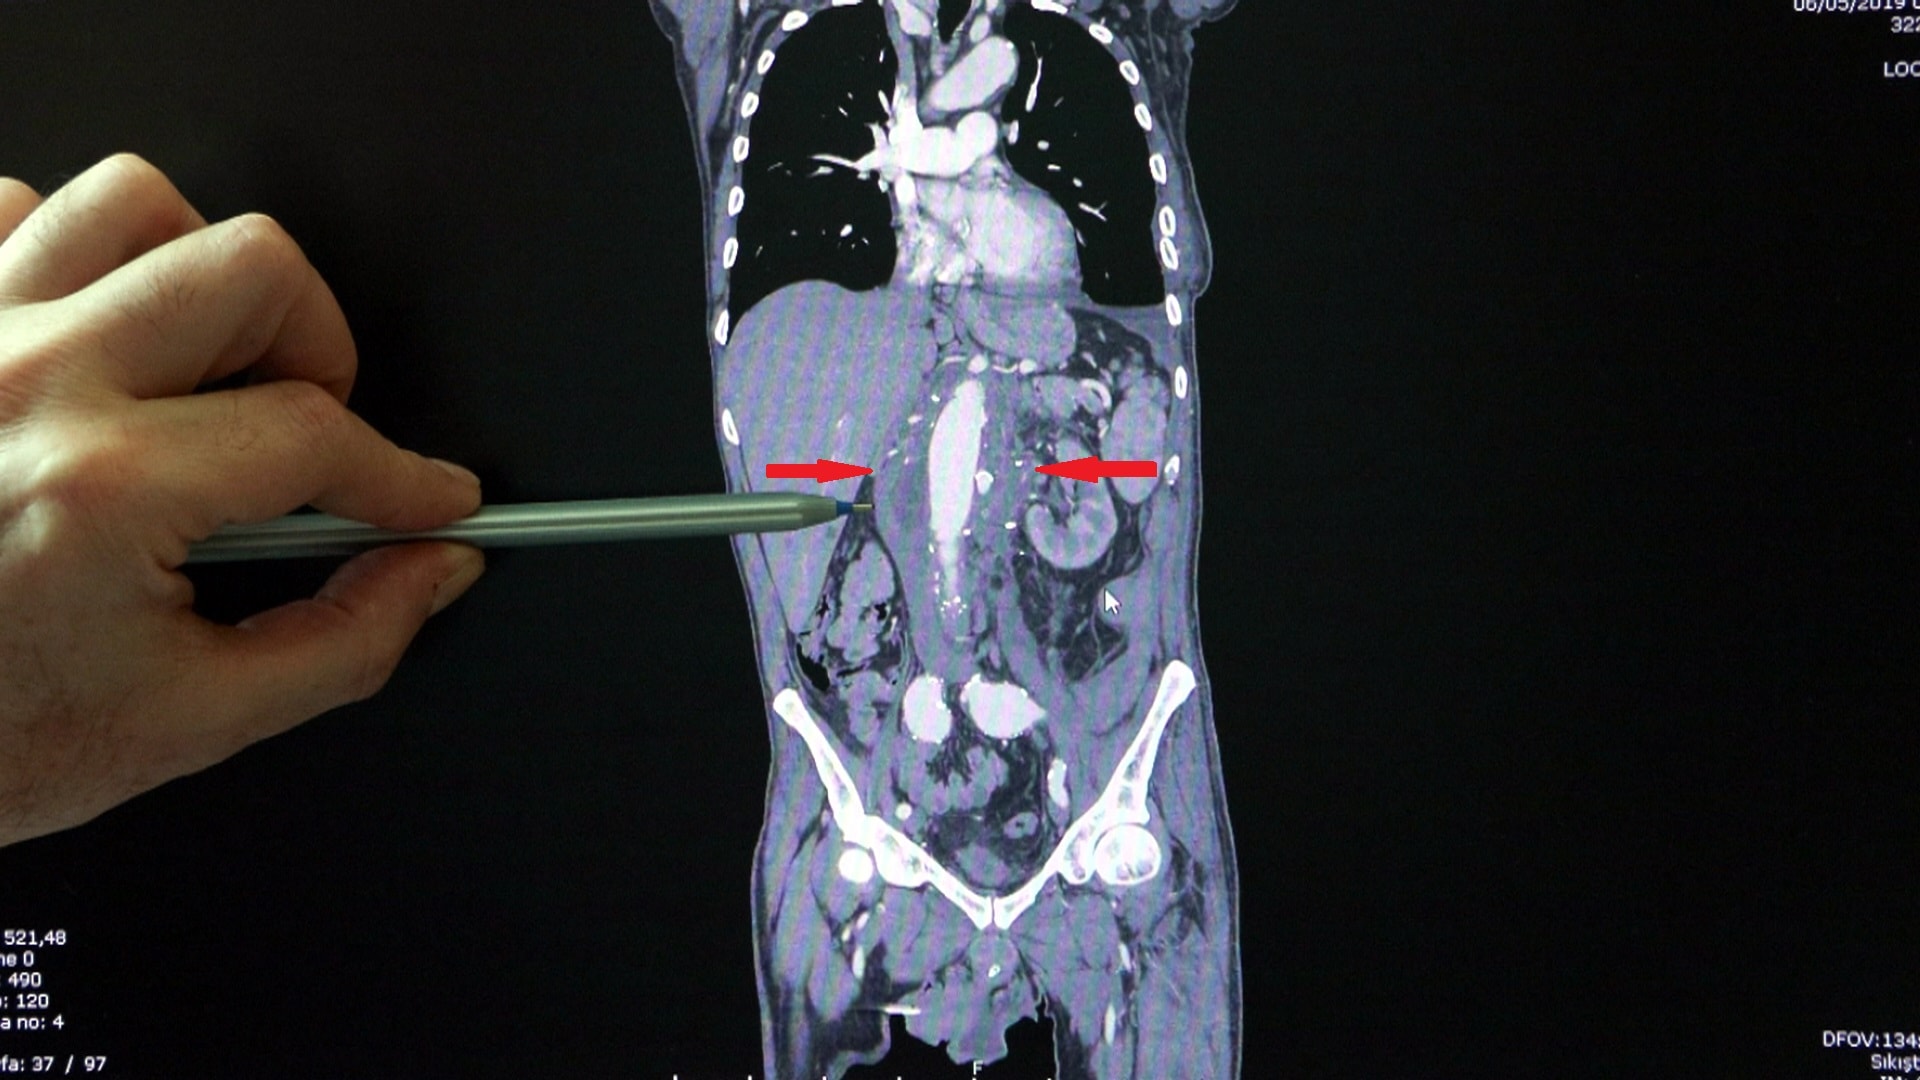

– Sıtkı Bey bize 5 yıl önce geldi, 3 ay önce bypass olmuştu. Karnında bir baloncuk şüphesi vardı. 3 santim olması gereken ana damar çapının yaklaşık 10 santime ulaştığını gördük. Anevrizma dediğimiz bu durum, aort damarının ya göğüs bölgesinde ya da karında olur. Ama Sıtkı Bey’de 60 santimlik aort damarının hepsinde genişleme vardı. Bütün iç organları ve bacakları besleyen hayati organ damarları da o baloncuğun içinden çıkıyordu. Patladı patlayacak durumdaydı.

– Biz o endişeyle ameliyat planlamasını yaptık. Genel cerrah, ürolog ve 3 kalp damar cerrahı girdik ameliyata. Yaklaşık 8-9 saat sürdü. İç organların hepsini ayrı ayrı sanki kan alıyorlarmış gibi, yapay beslenme ünitelerine bağladık. Sonra ana damarla iç organlara giden damarları tek tek birleştirdik. En sıkıntılı aşama buydu çünkü böbrek yetmezliği, karaciğer yetmezliği, bacaklarda felç, bacakların kesilmesi risklerinin hepsi vardı. Ameliyattan sonra en güzel an, ayaklarını oynatabiliyor olmasıydı. Bundan 2 yıl sonra sağ kasığı, ondan 6 ay sonra sol kasığı, ondan da 2 yıl sonra da göğüs duvarında ve çapın 7,5 santime ulaşan aort damarını kapalı ameliyatla tedavi ettik.

Korktuk acaba bütün o bölgeyi endovasküler stent dediğimiz yapay damarla kapatırsak felç olabilir mi diye. En son, 17-18 santimlik düz bir stent koyarak bütün göğüs duvarındaki anevrizmayı kapattık. Son ameliyatı da sol kasıkta olan baloncuğu için yine yine kapalı yöntemle yaptık. Sıtkı Bey’in kalpten çıkan ve kasıklara kadar giden 60 santimlik ana damarının yüzde 96’sına müdahale edildi. Bunun 90’ı yani yaklaşık 50-52 santimlik kısmı da yapay damarla değiştirilmiş oldu.